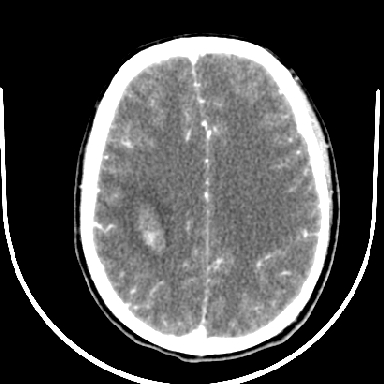

标题: CT6056:脑出血(血管畸形?)

m 40突发头痛左侧偏瘫3小时

考虑高血压性脑出血,依据:

1是高血压性脑出血的好发部位,形态呈肾形,是高血压性脑出血的常见形状

2增强时占位效应加重了,考虑出血还没有停止

3病灶周围水肿不是太厉害,一般肿瘤出血水肿多非常明显

4病灶周围的‘软组织’影没有明显的强化

5至于脑血管畸形引起的出血,暂时没有看到明显的畸形血管影,也不太支持

支持右侧基底节脑出血

右侧基底节区脑出血.

支持右侧基底节区(主要为外囊区)原发性脑出血。

另附部分资料:“血液溢出血管外形成血肿,其内含有大量血红蛋白、血浆白蛋白,球蛋白,因这些蛋白对x线的吸收系数高于脑质,故ct呈现高密度阴影,ct值达40~90h,最初高密度灶呈非均匀一致性,中心密度更高,新鲜出血灶边缘不清。基底节区血肿多为“肾”型,内侧凹陷,外侧膨隆,因外侧裂阻力较小,故向外凸,其它部位血肿多呈尖圆形或不规则形”